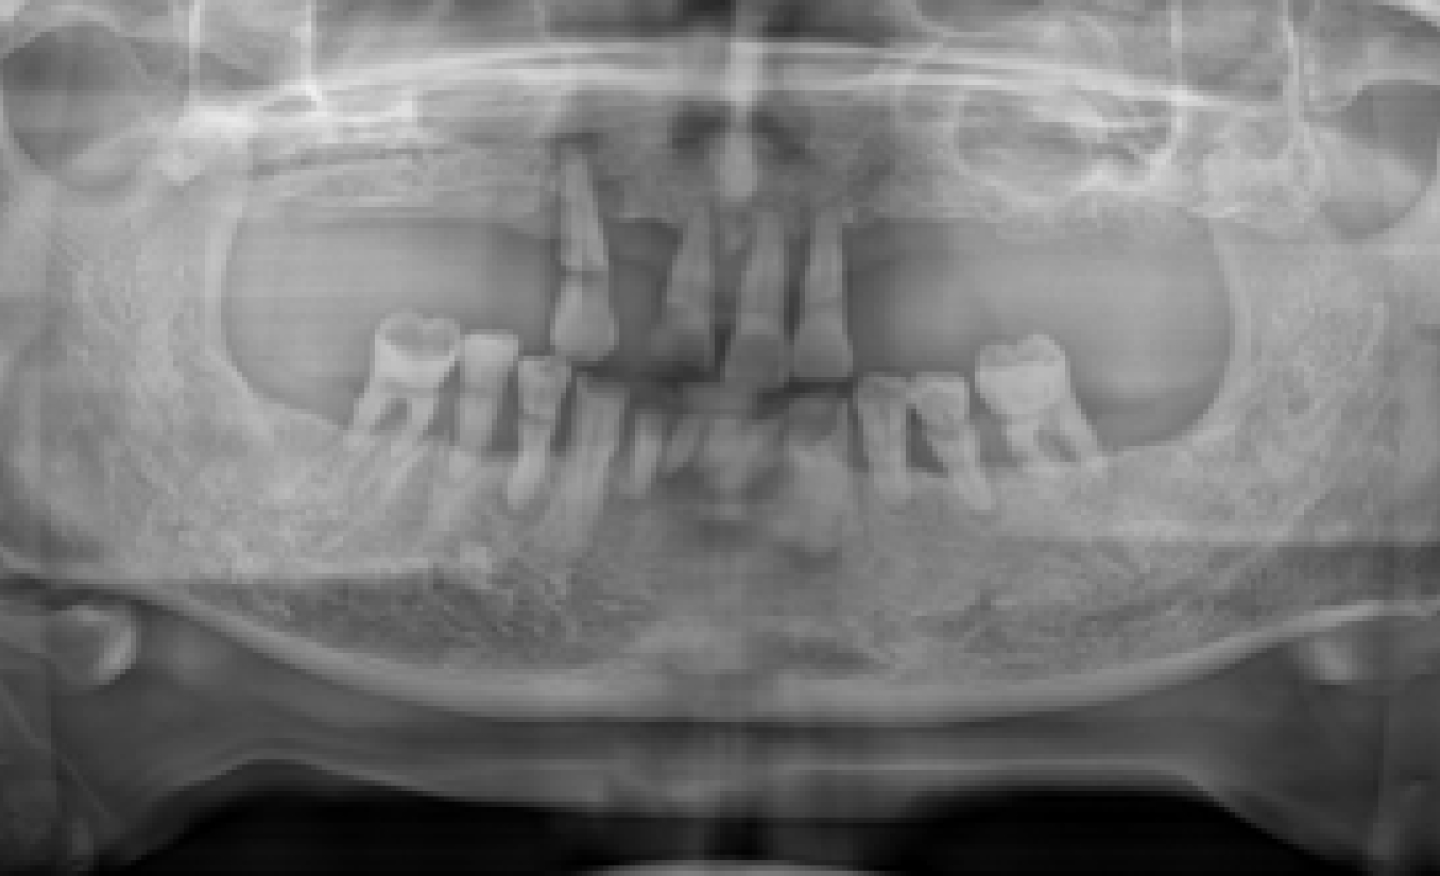

시흥치과 서울안심 전악 임플란트 즉시 임시치아 시술 전

BEFORE

전악 임플란트 + 즉시 임시치아

*위의 이미지는 동일한 조건에서 촬영되었으며 별도의 보정 작업을 거치지 않았습니다.

*모든 치료과정에서 부작용이 발생할 수 있으므로 정확한 진단과 수술이 요구됩니다.